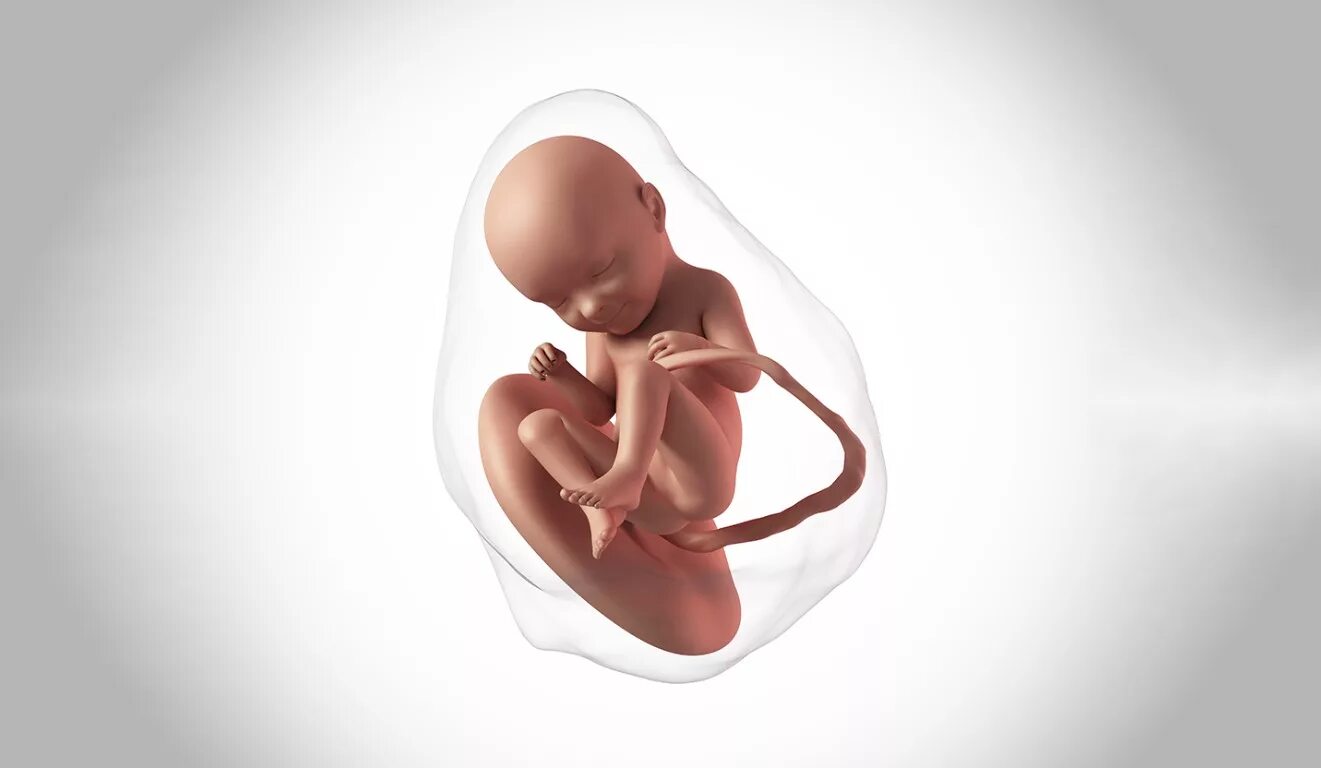

18 недель как выглядит малыш